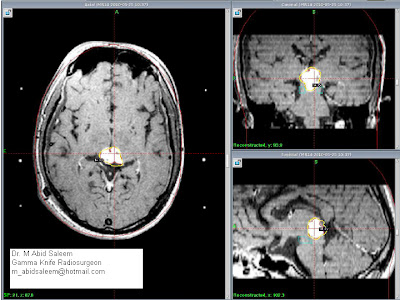

Pre Gamma Knife radiosurgery. Glomus jugulare Tumor. Volume 20.3 cc. |

.Patient was treated with marginal dose of 14 Gy

with 43% isodose line was prescribed for the target volume 20.3 cc; multiple

iso centers with 18, 14 and 8 mm collimators were used in APS and trunnion mode.